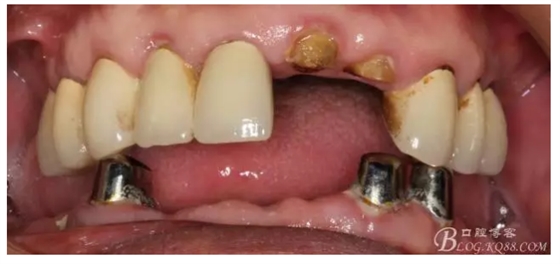

還要有足夠的牙本質(zhì)肩領(lǐng),大家現(xiàn)在可以看到患者的下頜套筒冠還是非常好的

修復(fù)后照片,

患者的口腔衛(wèi)生保持的不好,有大量的軟垢附著,

雖然牙根折斷了,但是從這張片子可以看出我們的套筒冠還是很堅挺的,有牙齦的退縮,但是牙槽骨致密程度非常好,值得欣慰

最近復(fù)查的照片,牙周維護(hù)好一些了,畢竟是一個80歲的老爺爺了,每次來拄著拐,還要跟著很多人攙扶著過來很不容易了。